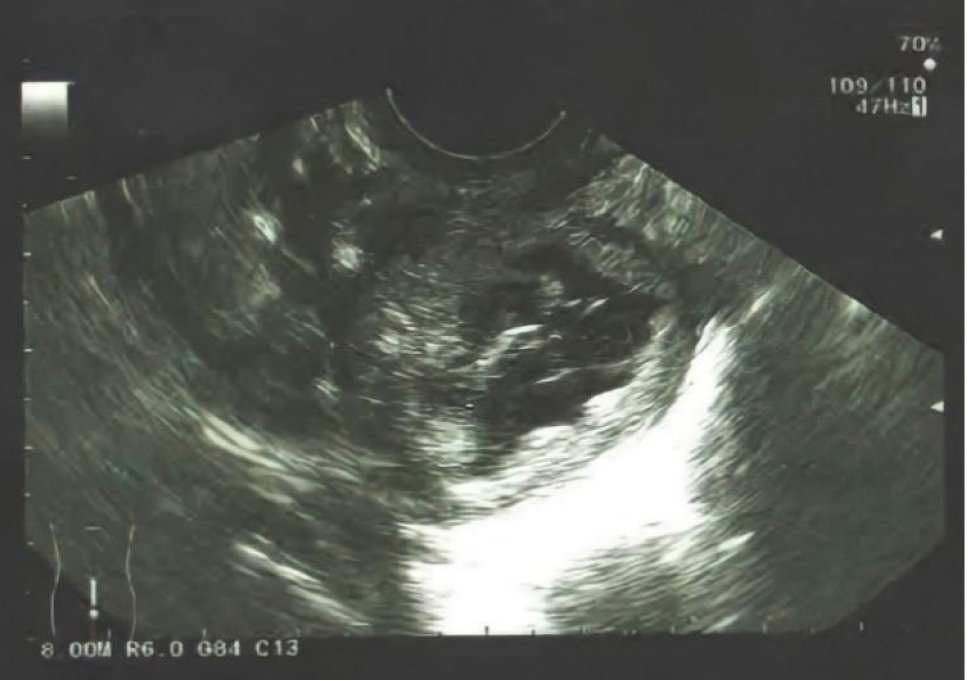

При МРТ: картина кистозно-солидного внеорганного гиповаскулярного объемного новообразования в позадиматочном пространстве, диаметром до 5 см. В марте 2021 года было проведено оперативное вмешательство: удаление объемного жидкостного образования в плотной капсуле. Гистологическое исследование: гранулема полости малого таза. На контрольном УЗИ в августе 2021 года (рис. 2) вновь выявлены признаки объемного образования малого таза, кровоток достоверно не визуализирован. Пациентка направлена на дальнейшее лечение в хирургическую клинику.

Рис. 2. Объемное образование позадиматочного пространства, принятое за рецидив гранулемы, кровоток достоверно не визуализирован